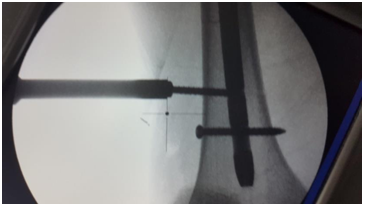

For change of entry point

1. Use Special sleeve with multiple options (Figure 10).

2. Eccentric reaming by awl while keeping the first Guide wire is possible.

Figure 10 For change of entry point.